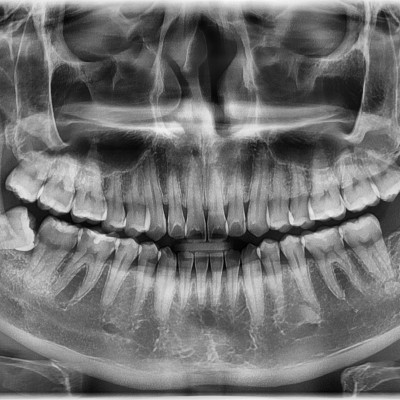

#28,38,48 사랑니 발치 N새글 #28,38,48 사랑니 발치 구강 외과 전문의가 당일 발치했습니다. -----------------------..